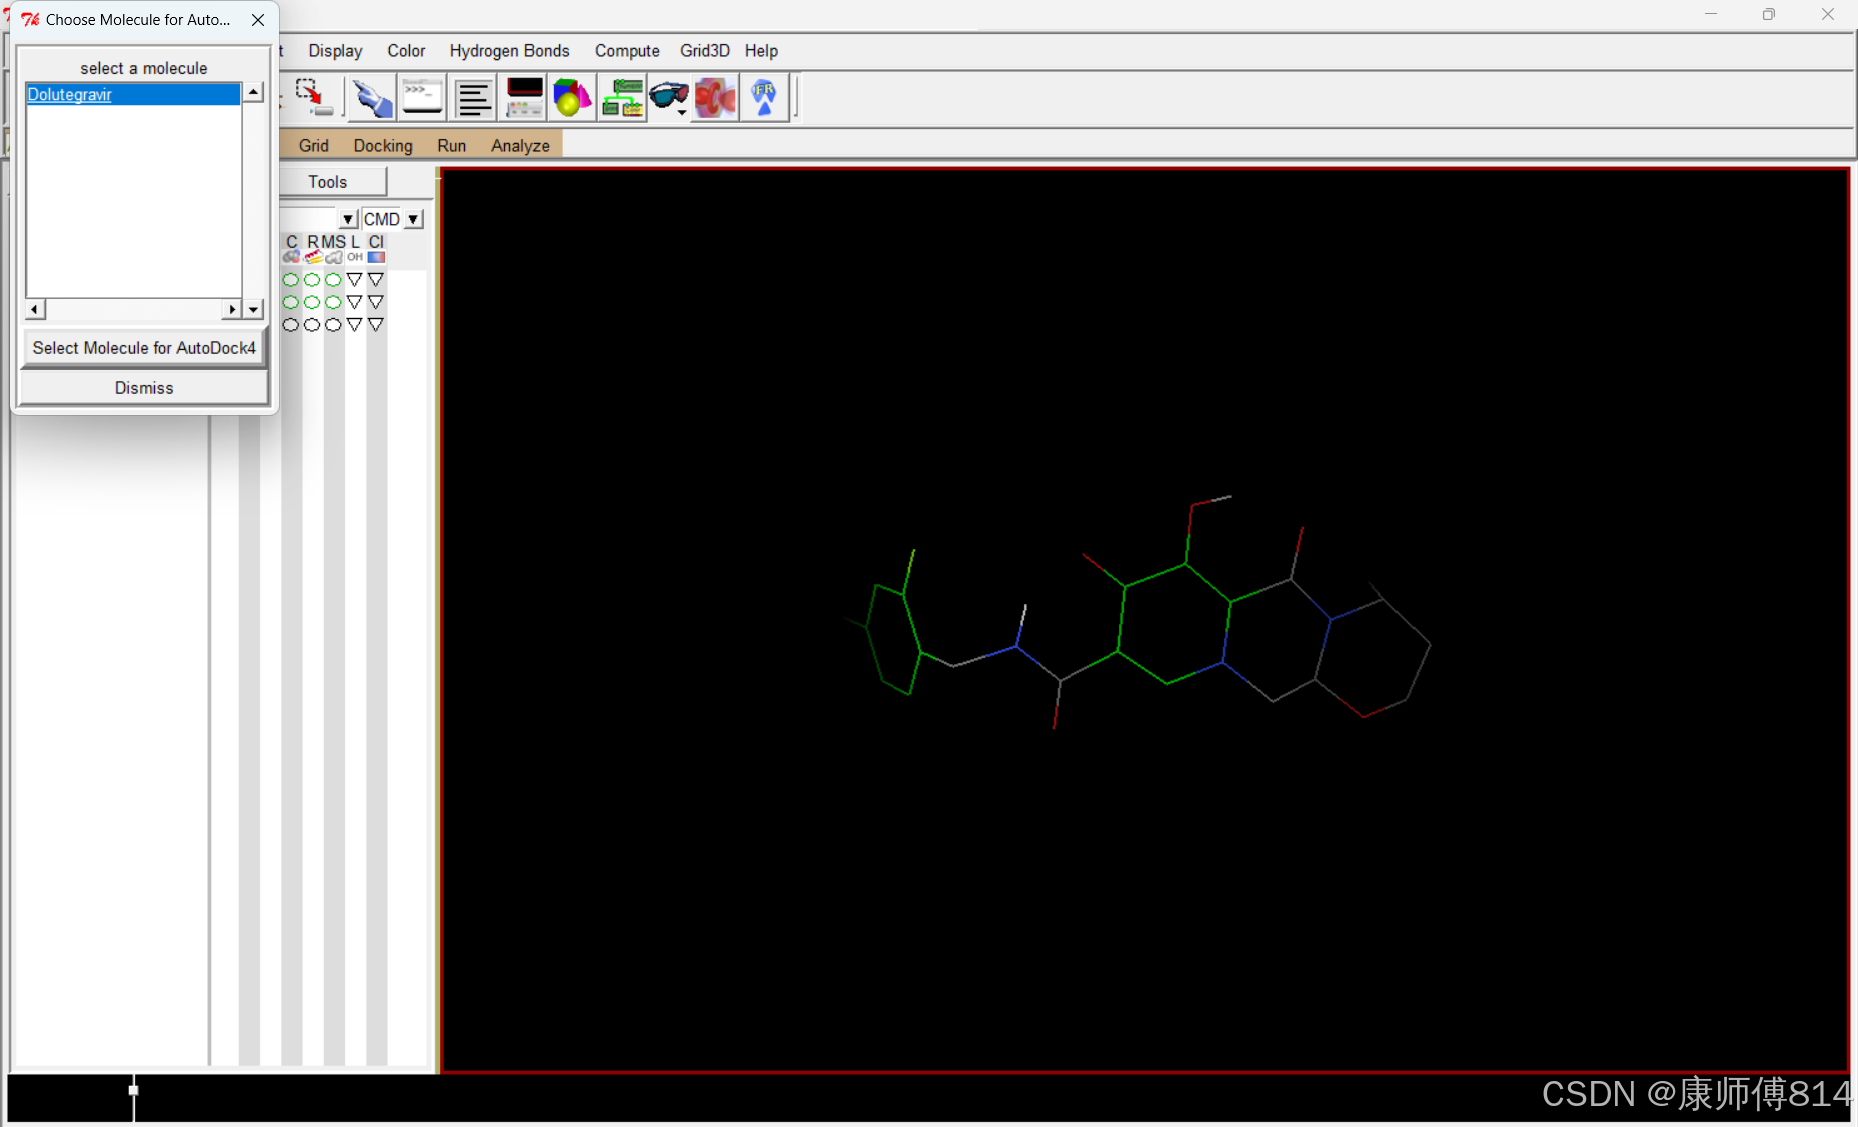

#选择小分子为配体

#点击Ligand-Input-Choose,点击小分子名称,点击Select Molecule for Autodock4,点击Ligand-Output-Save as PDBQT,保存为pdbqt文件